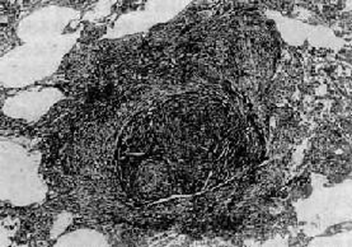

1.结节型矽肺:由于长期吸入游离二氧化硅含量较高的粉尘而引起的肺组织纤维化,典型病变为矽结节(silicoticnodule)。肉眼观,矽结节稍隆起于肺表面呈半球状,在肺切面多见于胸膜下和肺组织内,大小约为1~5mm。镜下观,可见不同发育阶段和类型的矽结节。早期矽结节胶原纤维细且排列疏松,间有大量尘细胞和成纤维细胞。结节越成熟,胶原纤维越粗大密集,细胞越少,终至胶原纤维发生透明性变,中心管腔受压,成为典型矽结节。典型矽结节横断面以葱头状,外周是多层紧密排列呈同心圆状的胶原纤维,中心或偏侧为一闭塞的小血管或小支气管。有的矽结节以缠绕成团的胶原纤维为核心,周围是呈漩涡状排列的尘细胞、尘粒及纤维性结缔组织。粉尘中游离二氧化硅含量越高,矽结节形成时间越长,结节越成熟,典型。有的矽结节直径虽很小,但很成熟,出现中心钙盐沉着,多见于长期吸入低浓度高游离二氧化硅含量粉尘进展缓慢的病例。淋巴结内也可见矽结节。

典型矽结节似“洋葱头”状结构 典型矽结节(“旋涡状”排列)